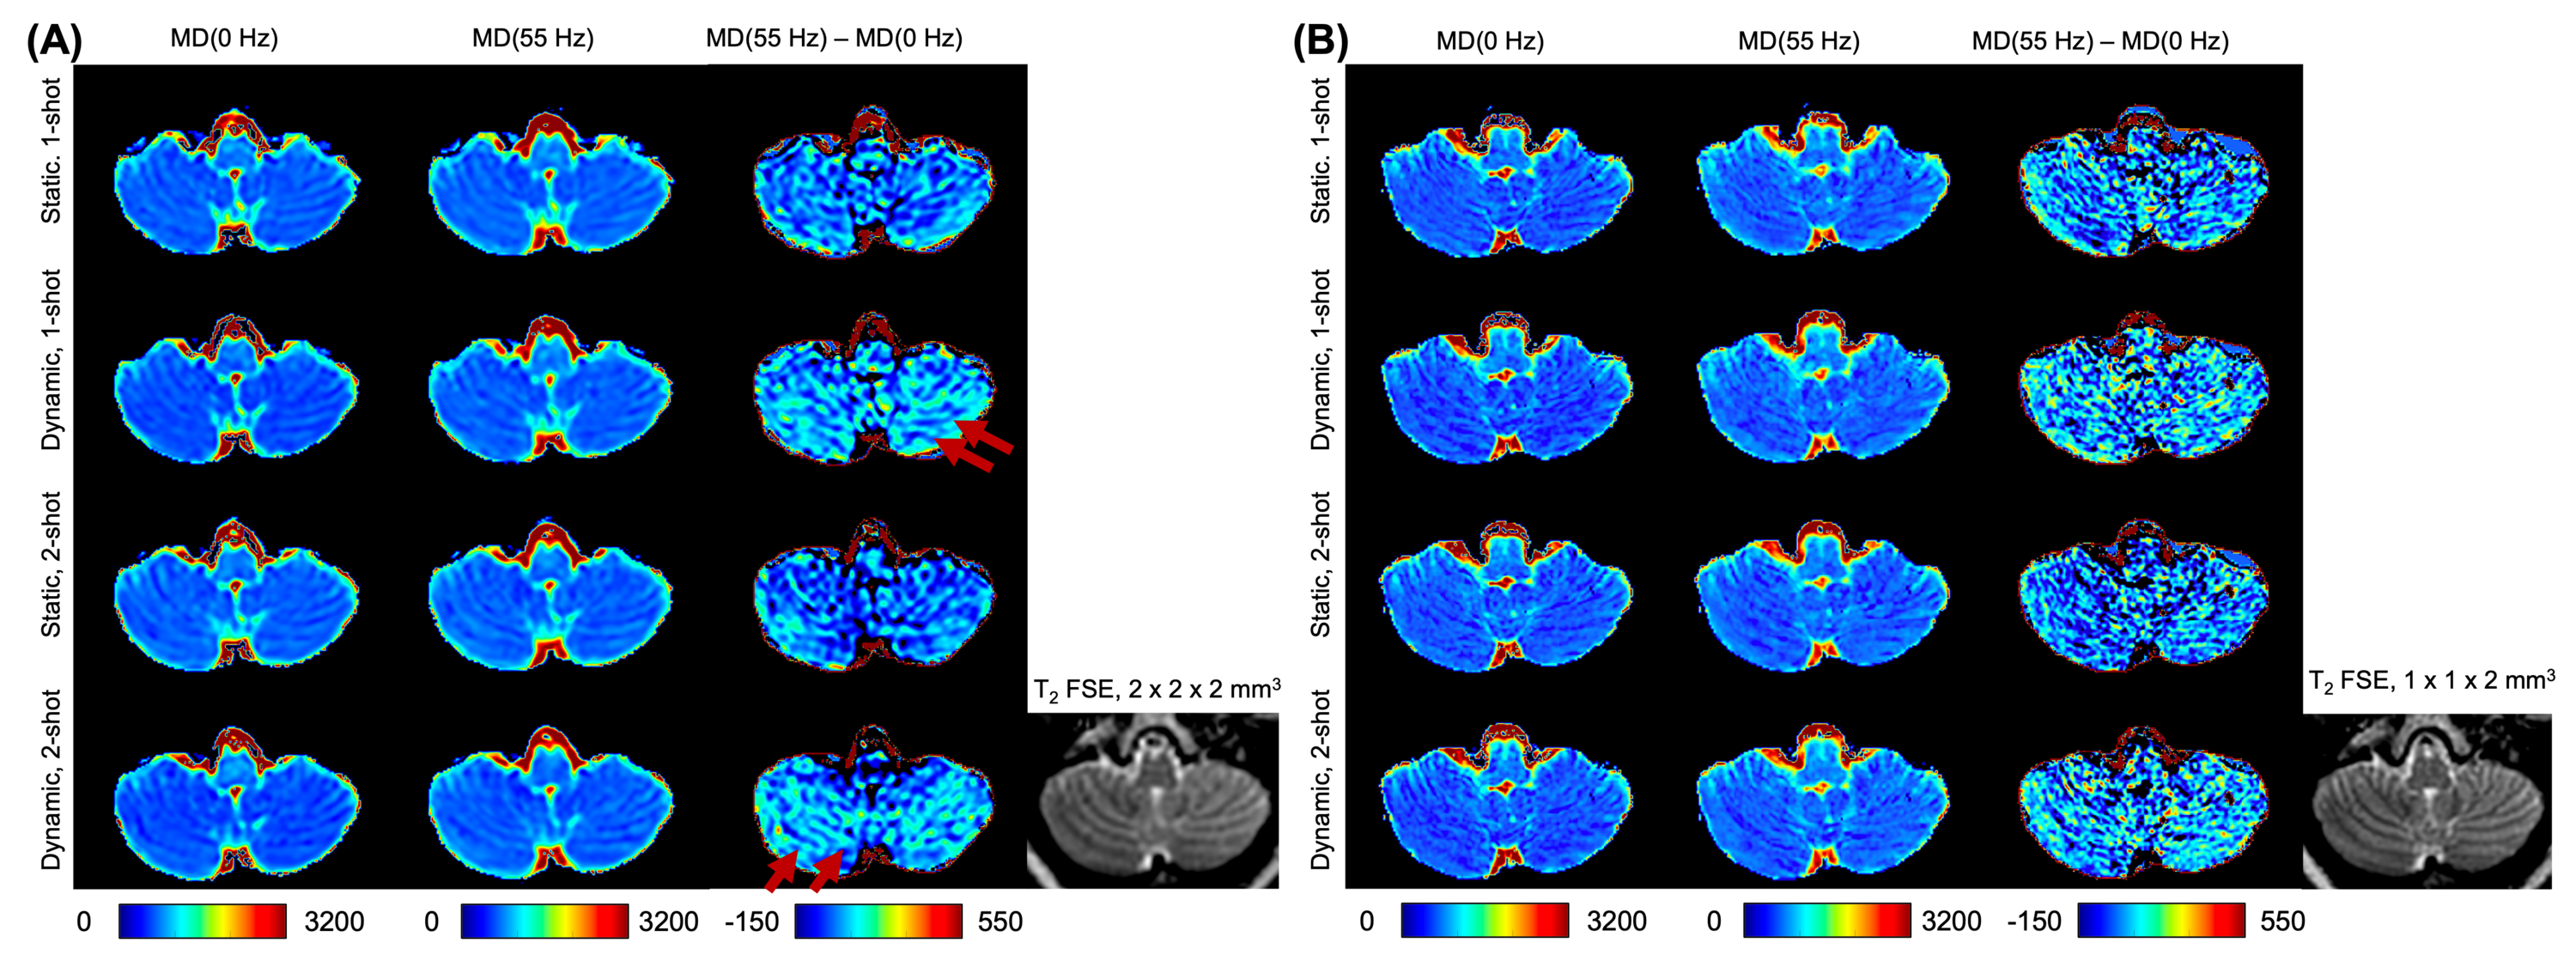

Figure 7 shows the axial view of cerebellum MD from the PGSE DTI (approximated as MD(0 Hz)) and the OGSE DTI at 55 Hz (i.e., MD(55 Hz)), and the difference between MD(55 Hz) and MD(0 Hz) at 2 x 2 x 2 (Figure 7A) and 1 x 1 x 2 (Figure 7B) resolutions. Cerebellar white matter (i.e., hypo-intensity regions in the FSE image) showed relatively high MD(0 Hz) and MD(55 Hz) acquired from all shimming approaches, whereas cerebellar grey matter (i.e., hyper-intensity regions in the FSE image) showed relatively low MD(0 Hz) and MD(55 Hz). In the MD difference map, more hyper-intensity regions that correspond to the cerebellar white matter regions in the FSE image (red arrows in Figure 7) were observed using the dynamic field shimming, compared to that using the static field shimming.

We have preliminarily demonstrated that FSE hypo-intensity regions in the cerebellum showed higher difference between MD at OGSE 55 Hz and MD at PGSE by acquiring diffusion MRI with dynamic field shimming, compared to that with static field shimming. Wu et al 17 has also shown FSE hypo-intensity regions, including the cerebellar granule cell layer, presenting high difference between ADC at OGSE 220 Hz and ADC at PGSE in the cerebellum of adult rats. Our study highlighted the potential to translate the characterization of fine layers in the cerebellum using high-resolution OGSE diffusion MRI with dynamic field shimming in humans. We acknowledge that the signal-to-noise ratio in MD(55 Hz)-MD(0 Hz) may not be sufficient for quantitative evaluation in this study. This is because we covered the whole brain for diffusion MRI to show the effectiveness of dynamic slice-by-slice shimming, which unfortunately limits the number of diffusion encoding directions in a feasible scan time. Future studies will optimize the imaging protocol, including the number of diffusion encoding directions, b-value, OGSE frequencies, and TE, to comprehensively characterize the time-dependent diffusion of the human cerebellum.